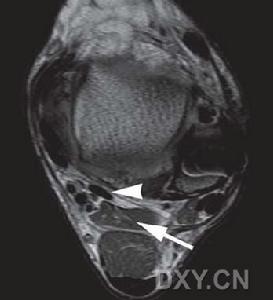

內耳門內耳門及周圍結構的形態及毗鄰關係,為乙狀竇後入路手術提供顯微解剖學依據。方法在5個新鮮國人頭顱標本上模擬枕下乙狀竇後手術入路,通過沖經內鏡和手術顯微鏡觀察內耳門及周圍結構的形態和毗鄰關係。測量內耳門後下緣到乙狀竇後緣中點和後半規管後緣中點的距離。結果內耳門位於岩骨內側面中央,面神經多位於內耳門的前上,聽神經位於其後下,小腦前下動脈在內耳門處形成動脈袢,發出1~3條內聽動脈。

內耳門後下緣到乙狀竇後緣中點的距離左側為(32.15±1.76)mm,右側為(33.34±1.57)mm;內耳門後下緣到後半規管後緣中點的距離左側為(12.51±2.15)mm,右側為(13.26±2.44)mm。結論熟悉內耳門及周圍結構的顯微解剖,有助於手術中保護重要結構,為聽神經瘤手術中保留面、聽神經功能提供了解剖學基礎。